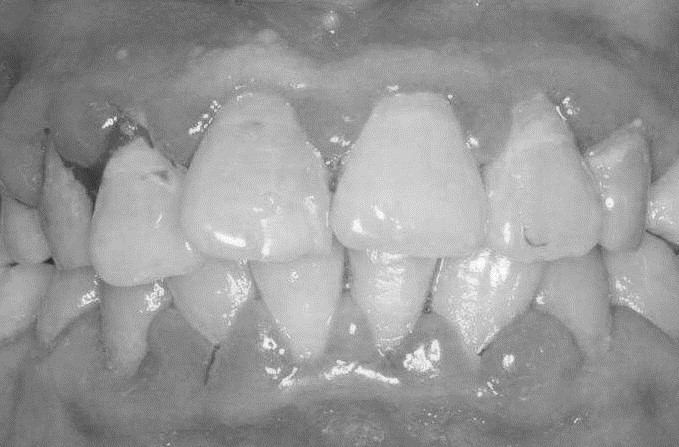

患者,女,52岁。因刷牙出血前来就诊。自述刷牙时牙龈出血2年余,有时吃苹果,馒头等食物时牙龈出血,近1个月早晨起床偶有唾液中带红色血丝。曾作常规血象检查,未见异常。无咬合不适或牙齿松动。检查可见全口牙石(+),有大量菌斑堆积,全口牙龈龈缘中度充血,龈乳头充血肿大,探诊出血明显,但无附着水平丧失,牙齿无松动,咬合关系未见异常。X线片显示全口牙槽骨无明显吸收。检查结果如下图:

(3)口腔检查:全口牙石(+),大量菌斑堆积,全口牙龈龈缘中度充血,龈乳头红肿,探诊出血。

(4)无附着丧失,牙齿无松动,咬合关系正常。

(5)X线片显示全口牙槽骨无明显吸收。